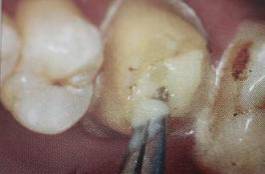

必要的情况下先开阔根管口建立一定的视角后,慢速手机上G钻为引导钻,由号递增引导开阔通路;P钻预备桩道,同样需要由小向大号递增,直到选择好适合的号预备到规定测量的深度即可,再配合纤维桩系统中各型号纤维桩所匹配的桩道钻,预备、修整成与纤维桩相适应的桩道。

预备后根管壁上会不同程度的牙胶和封闭剂等残留物,所以桩道预备前后建议X线片辅助检查预备深度等情况,而残留物也会很清晰地显现。